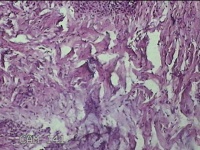

左侧腰部皮肤息肉组织

性别

男

年龄

40岁

临床诊断

皮肤和皮下组织良性脂肪瘤样肿瘤,其他部位的

一般病史

发现左侧腰部皮肤息肉组织5年余。

标本名称

大体所见

灰白暗红色息肉样组织1.7x1.3x0.3cm一块,表面糜烂,切面灰白暗红色,质软。